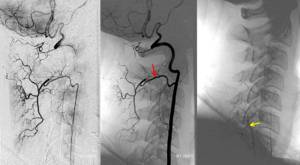

Стрелочкой указана пораженная артерия

Увеличенная часть иллюстрации демонстрирует место сжатия артерии.